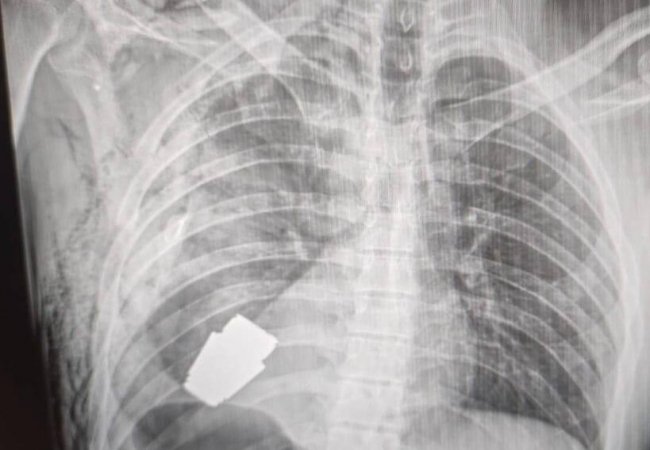

Героїчна операція: з тіла військовослужбовця дістали гранату, яка не розірвалася

Військові лікарі провели операцію з видалення гранати ВОГ, яка не розірвалася, з тіла військовослужбовця.

Гранату видалили у присутності двох саперів, які страхували безпеку медичного персоналу.

"Операція проводилася одним з найдосвідченіших хірургів ЗСУ — Андрієм Вербою без електрокоагуляції, оскільки граната могла детонувати у будь-який момент", — розповіла Маляр.

Оперативне втручання пройшло успішно, а пораненого військовослужбовця відправили на подальшу реабілітацію та відновлення.